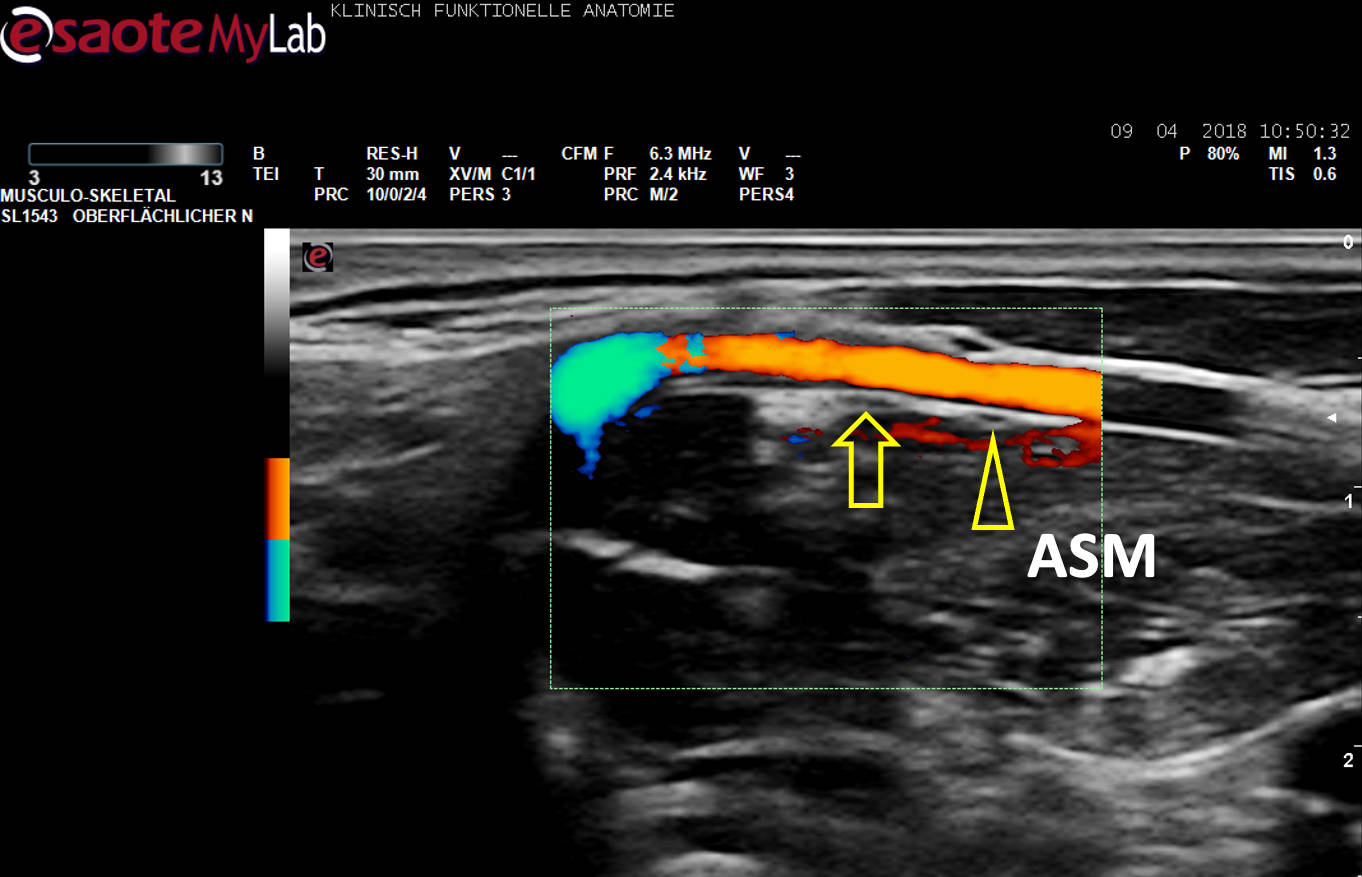

US-Darstellung eines N. phrenicus accessorius (Pfeilkopf) aus C5 auf dem M. scalenus anterior (ASM), ein Gefäß (Farbe) unterkreuzend. Pfeil: N. phrenicus aus C4.